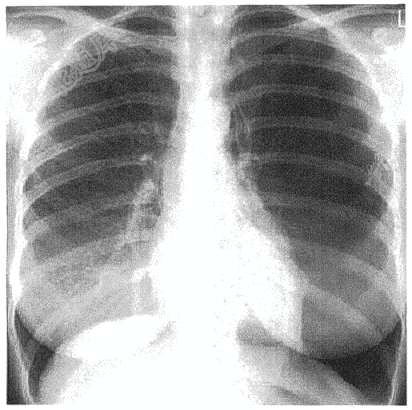

- 简答题患者女性,38岁,突发左侧胸痛半小时。